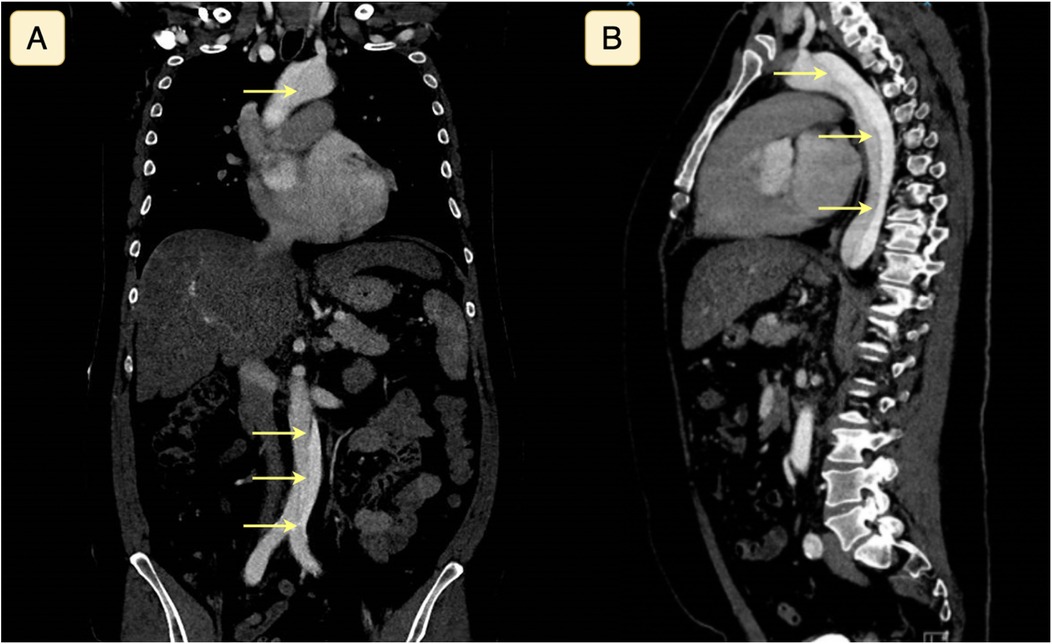

Non-contrast-enhanced computed tomography (CT) of the cerebrum revealed no intracranial abnormalities, including hemorrhage or ischemic lesions. Subarachnoidal hemorrhage was still suspected due to the thunderclap nature of the headache despite the normal CT scan of the cerebrum, while transitory cerebral ischemia was also considered a differential diagnosis. CT angiography of the cerebrum did not reveal any vascular abnormalities. Due to complaints of slight abdominal discomfort shortly after admission alongside the severe headache, CT angiography of the thorax and abdomen in the context of differential diagnostic purposes on the suspicion of aortic dissection was done, revealing a Stanford type A aortic dissection without concomitant affection of the carotid or vertebral arteries (Figure 1). Subsequent transthoracic echocardiography also visualized the extent of the aortic dissection from the aortic annulus to the femoral artery.

Figure 1. Computed tomography with angiography of the thorax and abdomen seen in coronal (A) and sagittal (B) plane, demonstrating a Stanford type A aortic dissection. The yellow arrows highlight the dissection plane separating the true and false lumina.